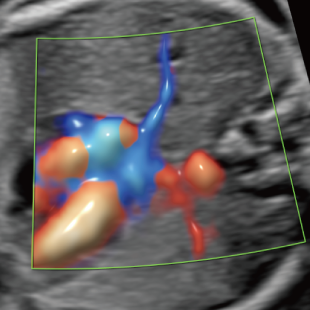

妊娠中期になると、胎児の体や内臓の構造がよりはっきりと確認できるようになります。 中期スクリーニングでは、頭部、顔面、頸部、胸部、腹部、心臓、手足、外性器、臍帯や胎盤など、全身をくまなく観察し、形態の状態を詳しく確認します。この頃に染色体数の変化を疑わせる所見が確認される事もあります。

胎児ドックの様子_中期_頭 胎児ドックの様子_中期_顔面 胎児ドックの様子_中期_心臓 胎児ドックの様子_中期_腹部 胎児ドックの様子_中期_足 胎児ドックの様子_中期_4D